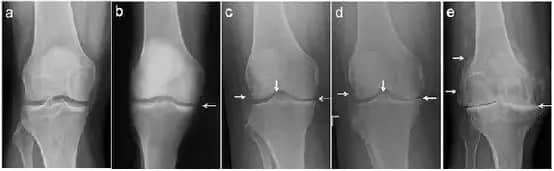

3、骨性关节炎:骨性关节炎是关节疼痛的常见原因,骨性关节炎多见于中老年人,而且常发生于手指和紧腰椎部位,关节炎是老年人常见疾病,关节炎可能是关节受寒受潮引起的,也可能是关节变形导致的,老年人要做好骨性关节炎的防治工作。